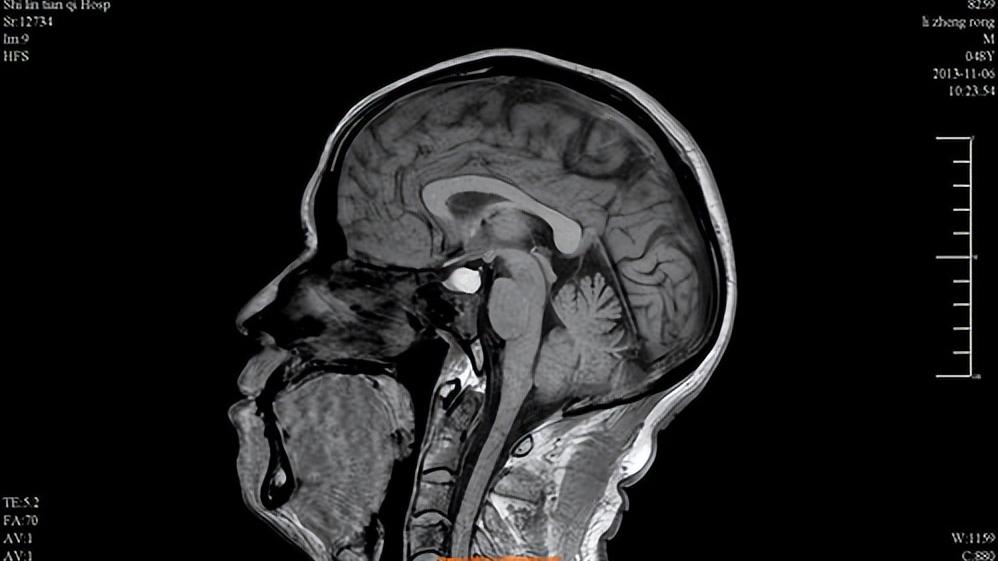

还有就是脑脊液流入蝶鞍的垂体窝,使蝶鞍扩大,持续压迫垂体。这时垂体不断受压缩小,也会导致闭经。而脑脊液外溢的因素很多,比如脑癌放疗、空蝶鞍综合征、腰椎穿刺刺破蛛网膜等。出现这种情况应尽早前往医院治疗,避免垂体功能长时间受影响导致不可逆的损伤。